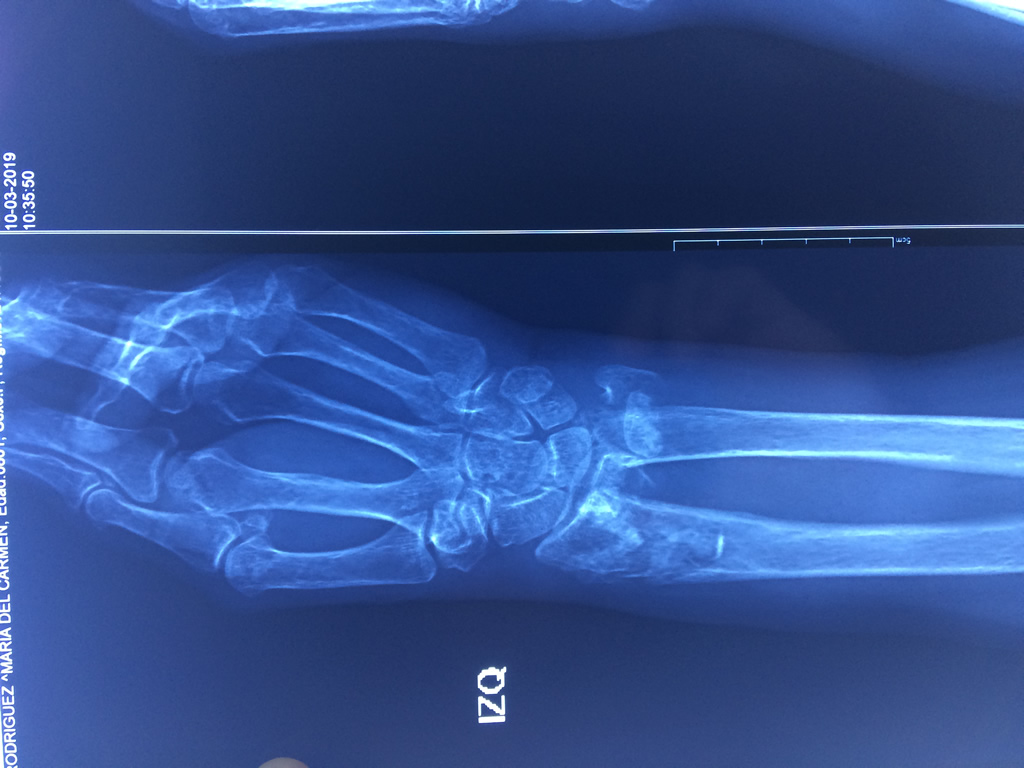

Cirugía de Fémur - Cirugías de Muñecas y Manos

Los procedimientos más comunes en cirugía de la mano son aquellos destinados a reparar traumatismos, incluyendo lesiones de tendones, nervios, vasos sanguíneos, y articulaciones; huesos fracturados; y quemaduras, cortes, y otros daños de la piel.